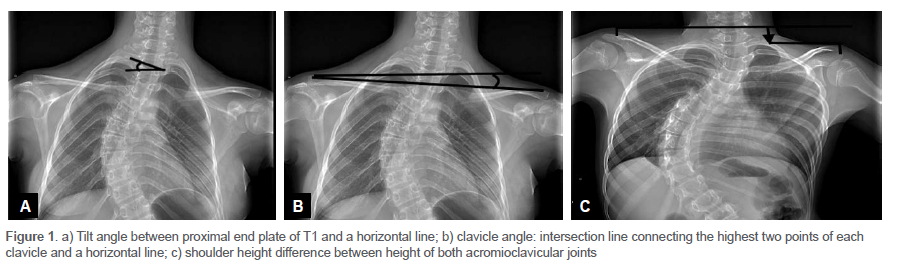

Further radiographic analysis included T1 tilt angle, clavicle angle and shoulder height (Figure 1). T1 tilt angle was defined as an angle between the proximal end plate of T1 and the horizontal.

Shoulder balance was determined from the clavicle angle, measured by the intersection of the line connecting the highest two points of each clavicle and the horizontal. Shoulder height was calculated by the difference of the acromioclavicular joints on both sides.10